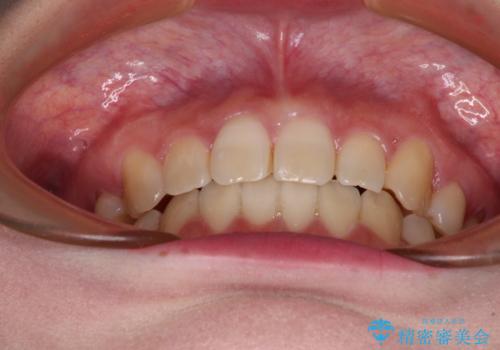

ディープバイトをインビザライン矯正で改善

- 前歯のデコボコと強い咬みしめを気にして来院された患者様です。

インビザラインを用いて、前歯の叢生を解消するとともに、ディープバイトを改善していくこととしました。

上顎に乳歯が左右1本ずつ残っていたため、若干咬み合わせに不具合が残りましたが、強い咬合力の原因であったディープバイトをしっかりと改善することができました。